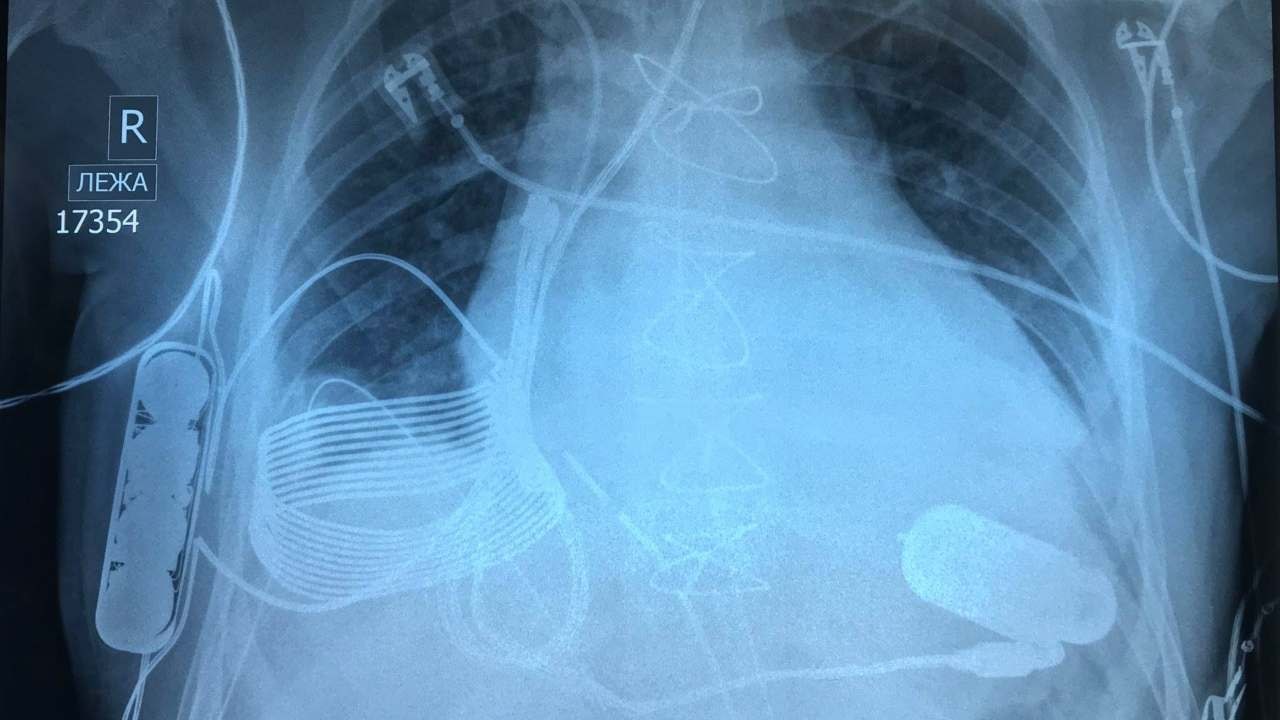

Rozwiązanie tego problemu zagwarantowała izraelska firma technologiczna Leviticus Cardio. Wykonane przez nich urządzenie zostało wyposażone w baterię, cewkę indukcyjną, a także wewnętrzny kontroler. Jedno ładowanie pozawala na osiem godzin pracy wszczepionego do klatki piersiowej serca. Aby je naładować należy założyć specjalną kamizelkę z wbudowaną cewką pozwalającą na ładowanie za pośrednictwem pola elektromagnetycznego. Do zbawiennego zestawu jest dołączony monitor na nadgarstek, który wskazuje poziom naładowania baterii oraz śledzi pracę implantu. | CHIP